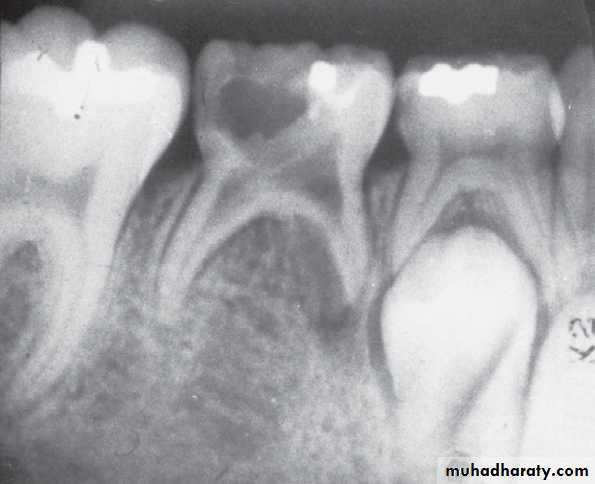

A, Pulp of the fi rst permanent molar was exposed by caries. The tooth was considered a candidate for the calcium hydroxide pulpotomy technique.

B, Calcifi ed

bridge has formed over the vital pulp in the canals.C, Continued

root development and pulpal recession are indicative of continuing pulpal vitality. The crown should be supported with a full-coverage restoration.Mature and immature teeth in the x-ray

Internal resorption after calcium hydroxide pulpotomy in a primary tooth

Deep caries in the first primary molar and due to that caries resorption in the bifurcation areaDeep caries in the mandibular second primary molar

Periapical radiographs